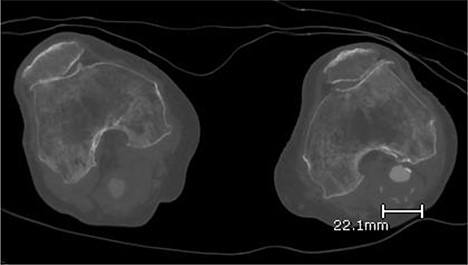

A 92-year-old female, independent from home, presented after multiple falls due to a four-month history of left foot drop. The foot drop had gradually worsened to the point that there was complete paralysis of ankle dorsiflexion and was associated with significant oedema of the foot. On examination, there was a large pulsatile mass in the popliteal fossa bilaterally. All peripheral pulses were palpable without any signs of ischemia. The most striking examination finding was complete paralysis of left ankle dorsiflexion with 0 out of 5 power. Ultrasound revealed that there were (Fig 1) bilateral popliteal artery aneurysms, which was larger on the left, causing displacement and impingement of the common peroneal nerve at the knee crease (Fig 2). Further computed tomography angiogram demonstrated an unruptured left PAA measuring 22 × 21 mm in maximal dimension over a distance of 24 mm (Fig 3). Intraluminal thrombus was also noted with 60% luminal stenosis. Distally, the arteries were heavily calcified with two-vessel runoff at the ankle. An emergency endovascular repair of the left PAA was performed by using 8 mm × 15 cm and 7 mm × 10 cm Gore Viabahn stents (Fig 4). The stents were deployed after a balloon-angioplasty and adequate decompression of the aneurysm was achieved. The postoperative period was uneventful, and patient’s pre-existing aspirin was continued. The leg and foot oedema improved rapidly over the subsequent few days. At follow-up in 12 weeks, the patient showed some return of motor function of the ankle and was walking with ankle splint. Her left leg remained well perfused with palpable pulses.

Computed topography angiogram image of left popliteal artery aneurysm, measuring 21 × 22 mm (AP × RL).